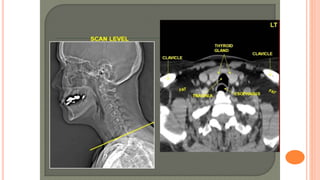

(2) CT

CT at level of Aortic Arch

CT at levelof Aortic Arch